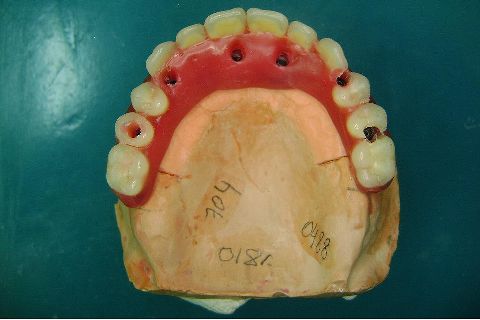

Atualização do caso clínico que já postei, "REABILITAÇÃO EM MAXILA ATRÓFICA COM IMPLANTES", um caso que inclui expansão do rebordo estreito com cinzel e martelo, expansores rosqueáveis, enxerto e instalação dos implantes distais inclinados tangenciando seio maxilar. Inclui esvaziamento do forame nasopalatino e preenchimento com biomaterial para instalação de dois implantes próximos dele. Cirurgia realizada em única sessão, com instalação dos 6 implantes. Para os colegas que não conheceram e/ou esqueceram da apresentação, este é o resumo do caso na fase cirúrgica.http://www.youtube.com/watch?v=BtvexFexRPA&hd=1

FASE PROTÉTICA DA REABILITAÇÃO EM MAXILA ATRÓFICA...incluindo a reabertura, instalação dos minipilares e PTR provisória reembasada sobre os cilindros de proteção.